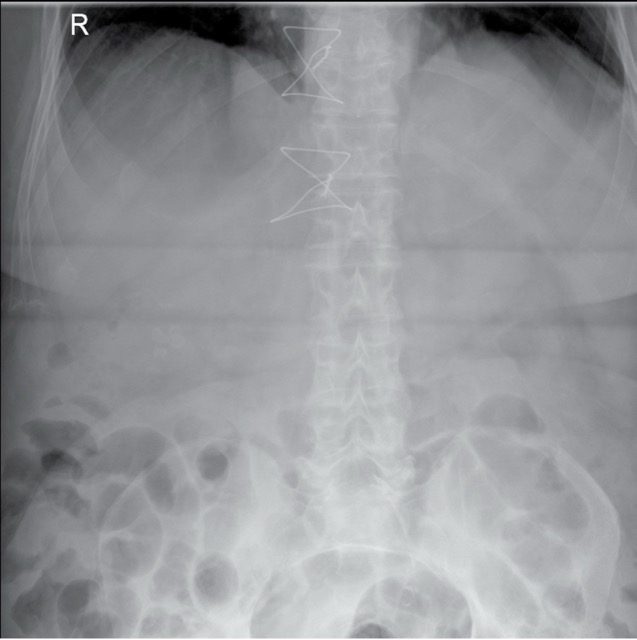

Abdomen

4 pattern guides